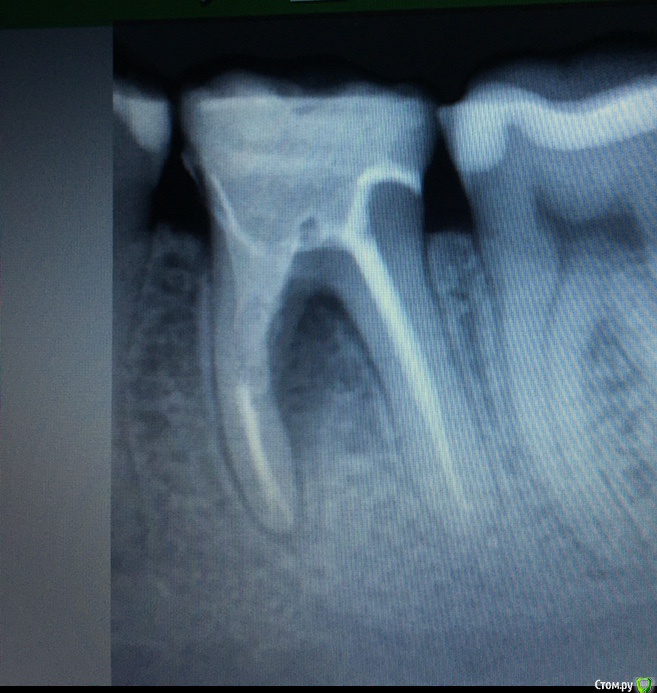

Евагэпс Опубликовано 15 ноября, 2018 Поделиться Опубликовано 15 ноября, 2018 Обнаружила у себя на десне возле депульпированного зуба с керамической вкладкой белесое образование в виде шишки. При надавливании болезненное. Температура 37.1, но нахожусь в тропическом климате, у моей подруги тут такая же. Повреждений десны не было.Вкладка стоИт три месяца.Прилагаю рентгеновский снимок зуба двухнедельной давности и сегодняшнее фото десны. Нахожусь на Шри-Ланке. Тут все оочень плохо с медициной. Прошу дистанционной помощи.Из лекарств с собой есть антибиотики, фурацилин и метрагил дента. Ссылка на комментарий

Neilrus Опубликовано 15 ноября, 2018 Поделиться Опубликовано 15 ноября, 2018 Обнаружила у себя на десне возле депульпированного зуба с керамической вкладкой белесое образование в виде шишки. При надавливании болезненное. Температура 37.1, но нахожусь в тропическом климате, у моей подруги тут такая же. Повреждений десны не было.Вкладка стоИт три месяца.Прилагаю рентгеновский снимок зуба двухнедельной давности и сегодняшнее фото десны. Нахожусь на Шри-Ланке. Тут все оочень плохо с медициной. Прошу дистанционной помощи.Из лекарств с собой есть антибиотики, фурацилин и метрагил дента.Начинается гнойный процесс в области где корни расходятся. По возвращению домой зуб необходимо удалить, к сожалению, чтобы не удалять там где вы находитесь можете "задавить" процесс антибиотиками Ссылка на комментарий

Евагэпс Опубликовано 15 ноября, 2018 Автор Поделиться Опубликовано 15 ноября, 2018 Начинается гнойный процесс в области где корни расходятся. По возвращению домой зуб необходимо удалить, к сожалению, чтобы не удалять там где вы находитесь можете "задавить" процесс антибиотикамиЭто то, что черное на снимке между корней? А на фото внешнее проявление этого? Антибиотки начала пить сегодня утром.Я этот снимок специально делала перед отъездом, так как недавно ставила вкладку. И врач отпустил меня со спокойной душой( Ссылка на комментарий

DmitrySH Опубликовано 16 ноября, 2018 Поделиться Опубликовано 16 ноября, 2018 Диагноз: периодонтит Ссылка на комментарий

Neilrus Опубликовано 16 ноября, 2018 Поделиться Опубликовано 16 ноября, 2018 Через 3 месяцамноговато, даже если сейчас задавите АБ, то через месяц может опять "раздует"...серфинг, все делаДа, периодонтит Ссылка на комментарий